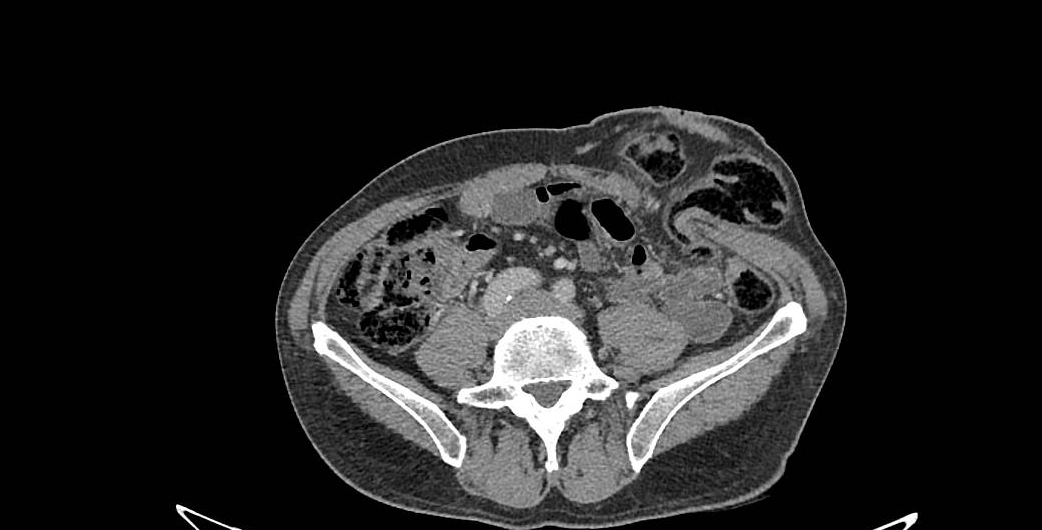

Factors that can contribute to causing a stoma hernia to occur include coughing, being overweight or having developed an infection in the wound at the time the stoma was made. The development of a stoma hernia is often a gradual phenomenon, with the area next to the stoma stretching and becoming weaker with the passage of time. This weakness, or gap, means that every time one strains, coughs, sneezes or stands up, the area of the abdomen next to the stoma bulges, or the whole stoma itself protrudes as it is pushed forwards by the rest of the abdominal contents behind it.

They may make it difficult to attach a bag properly and sometimes their sheer size is an embarrassment as they can be seen beneath clothes. Although a rare complication, the intestine can sometimes become trapped or kinked within the hernia and become obstructed. Even more seriously the intestine may then lose its blood supply, know as strangulation. This is very painful and requires emergency surgery to untwist the intestine and prevent the strangulated part of the bowel from being irreversibly damaged. Regardless of inconvenience or pain, hernias are defects in the abdominal wall and should not be ignored simply because they might not hurt.